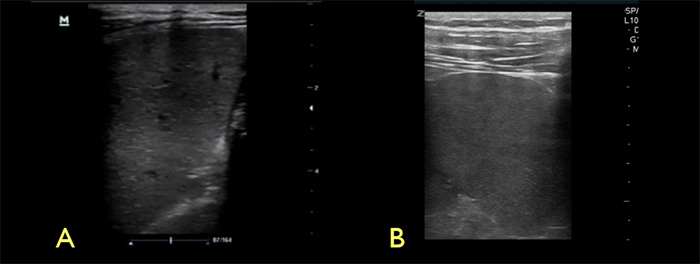

- If no lesions are noted, switch to the high frequency linear transducer to evaluate the spleen for small focal hypoechoic lesions. (Video 5)

Video 5. Normal spleen with linear probe

Figure 4. Spleen with low frequency (A) vs high frequency (B) transducers

Figure 10. Spleen with high frequency linear transducer, A- microabscesses and granulomatous infiltration, B- normal spleen echotexture

- The use of a high frequency linear transducer can improve your ability to identify splenic micro abscesses. 21,26-8 Freezing the image and scrolling manually can slow the image down enough to identify small micro abscesses (Figure 8).